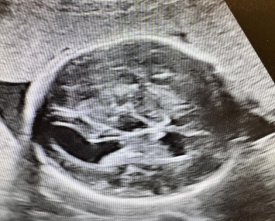

见于1-3%正常胎儿,可单发,亦可多发,脉络丛囊肿与18-三体综合征相关。孤立性脉络丛囊肿预后良好,发现时,应进行非整倍体尤其是18-三体综合征的筛查③,低风险者常规产前随诊,高风险者仍需行介入性诊断。非孤立性脉络丛囊肿应行介入性诊断,排查胎儿染色体异常可能。